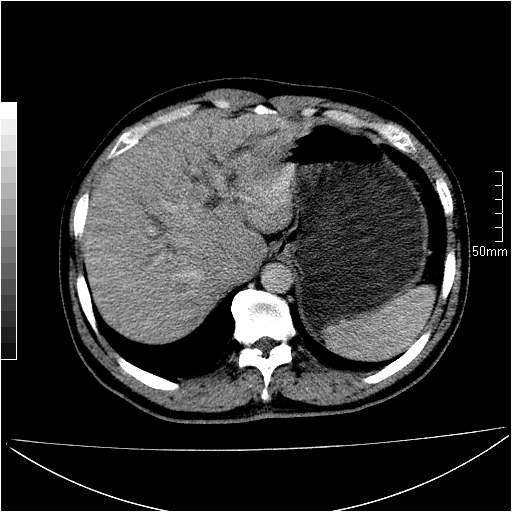

男性,54岁,皮肤黄染,搔痒一周余.b超示肝左叶回声异常.初步诊断1胆总管下段结石2胆囊结石伴慢性胆囊炎请各位战友帮忙看一下肝脏多发低密度如何解释恰当.增强效果不是很好.请大家见谅.

胆总管及肝内胆管扩张,考虑是结石!但,肝内的低密度区增强不明,可能是肝ca,因为肝ca在增强时呈快进快出.另年胆总管扩张原因,可以考虑一下是不是,胆管ca.再次要考虑肝内的低密度是否为海绵状血管瘤所致!

首先,胆总管下端结石梗阻伴肝内胆管扩张可确定。

另外,肝八段低密度占位,呈多灶性,考虑肝脓肿或肝癌可能,(图像质量欠佳)建议进一步检查。

既然做了增强,为什么光提供延时期片子,肝动静脉期肝右叶前下段病灶增强如何?另外胆囊壁增厚,欠规整,内密度不均,与肝右叶病灶分界不清,增强表现怎样?肝内胆管轻度扩张,胆总管扩张,但未见明显结石影,也应提供增强早期图像才好鉴别扩张原因。片子较清,但不够完整,暂考虑1.胆囊癌肝局部浸润,或肝癌胆囊侵犯,2.胆总管下端或胰头钩突部占位。总之本人看不明白,请高手画图指示,先谢了!

由于胆囊窝内结构显示不清,肝脏病灶又邻近胆囊窝首先考虑胆囊癌肝受侵犯。而后因肝脏病灶强化有渐进改变,且相邻胆管扩张,故考虑肝胆管细胞癌待排。

左肝胆管细胞癌。

胆总管下端结石。